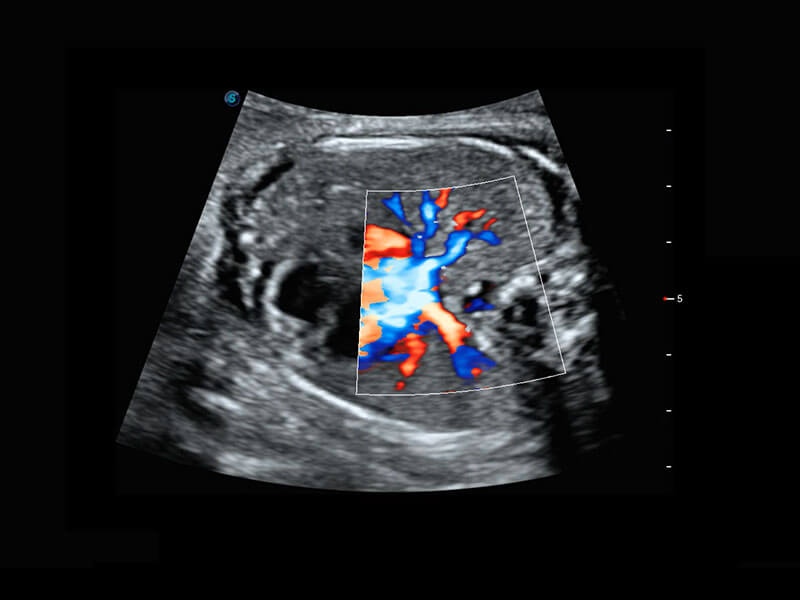

P60搭載寬頻帶線陣探頭、寬景成像、彈性成像技術(shù),為您提供乳腺應(yīng)用方案。P60支持高頻相控陣探頭、線陣探頭、腹部高頻探頭、腹部微凸探頭等,豐富的探頭群搭載敏感的彩色血流成像,適用于新生兒多種臟器檢測要求,滿足新生兒篩查需求。

乳腺癌顯微血流